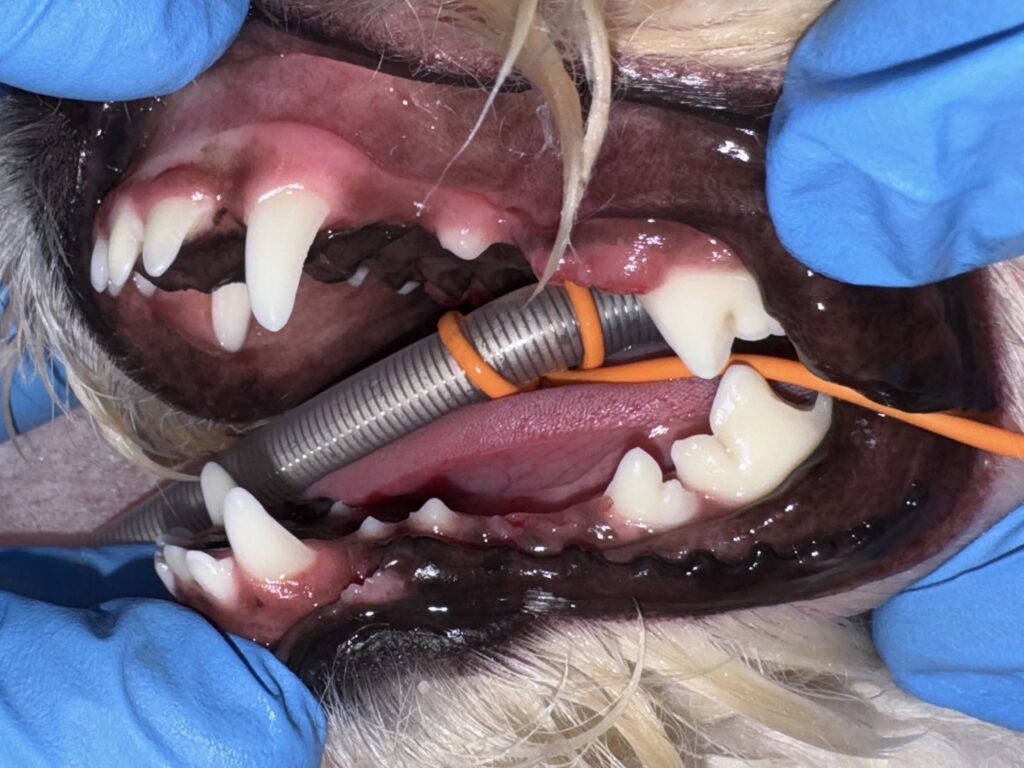

・After

歯肉の縁の下まで破折していたため、今回は抜歯が適応となりました。

抜歯後は抜歯部位を歯肉フラップを作成し、歯肉縫合しました。